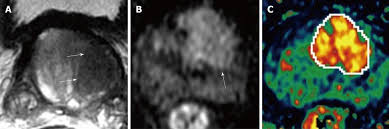

Cancers Free Full Text Correlation Between Intraprostatic Psma Uptake And Mri Pi Rads Of 68ga Ga Psma 11 Pet Mri In Patients With Prostate Cancer Comparison Of Pi Rads Version 2 0 And Pi Rads Version 2 1 Html

Cancers Free Full Text Correlation Between Intraprostatic Psma Uptake And Mri Pi Rads Of 68ga Ga Psma 11 Pet Mri In Patients With Prostate Cancer Comparison Of Pi Rads Version 2 0 And Pi Rads Version 2 1 Html from www.mdpi.com